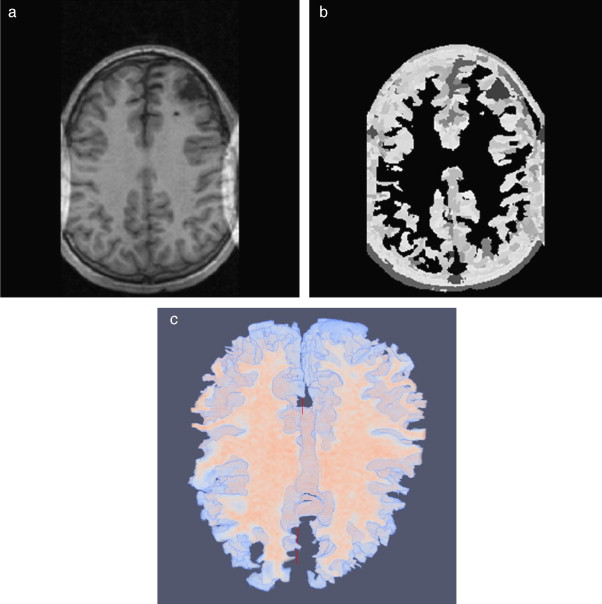

En la figura 20 se presentan los resultados obtenidos por cada etapa en imágenes médicas de IRM del cerebro en formato DICOM, 60 slices , tamaño de 256 × 256 pixels, voxel spacing: 0,86 × 0,86 mm × 3,0 mm . Por efectos de visualización, solamente se presenta uno de los cortes axiales utilizados. Obsérvese en la figura 20 .b la selección de cuatro semillas sobre la zona de interés, las cuales fueron asignadas de manera arbitraria. El éxito de la segmentación dependerá del lugar donde se coloquen estas semillas.

|

Figura 20. Segmentación de materia blanca empleando Region Growing en IRM del cerebro. (a) Volumen de IRM cerebral original. (b) Vista de un corte axial con la lección de cuatro semillas iniciales. (c) Imagen (b) filtrada con difusión anisotrópica. (d) Vista del corte axial (b) con la materia blanca segmentada a través de Region Growing . (e). Vista volumétrica de la materia blanca segmentada en (d). |